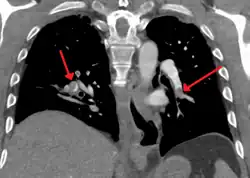

Prognosis

Large saddle embolus seen in the pulmonary artery (white arrows)

Fewer than 5 to 10% of symptomatic PEs are fatal within the first hour of symptoms.[38][92]

There are several markers used for risk stratification and these are also independent predictors of adverse outcomes. These include hypotension, cardiogenic shock, syncope, evidence of right heart dysfunction, and elevated cardiac enzymes.[38] Some ECG changes including S1Q3T3 also correlate with a worse short-term prognosis.[24] There have been other patient-related factors such as COPD and chronic heart failure thought to also play a role in prognosis.[38]

Prognosis depends on the amount of lung that is affected and on the co-existence of other medical conditions; chronic embolisation to the lung can lead to pulmonary hypertension. After a massive PE, the embolus must be resolved somehow if the patient is to survive. In thrombotic PE, the blood clot may be broken down by fibrinolysis, or it may be organized and recanalized so that a new channel forms through the clot. Blood flow is restored most rapidly in the first day or two after a PE.[101] Improvement slows thereafter and some deficits may be permanent. There is controversy over whether small subsegmental PEs need treatment at all[102] and some evidence exists that patients with subsegmental PEs may do well without treatment.[64][103]